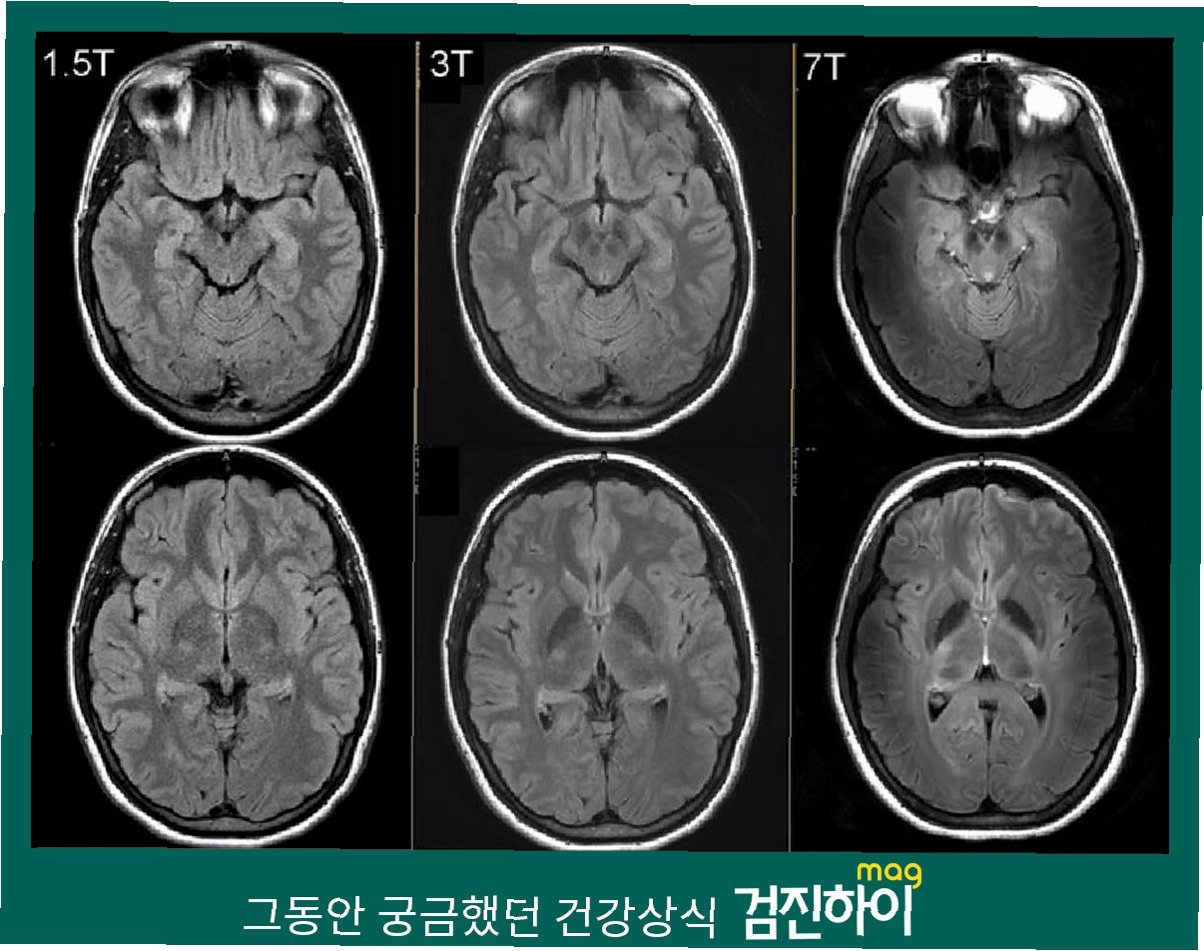

MRI(자기공명영상장치)는 강력한 자력을 이용하여 신체 내부를 촬영하는 의료 기기입니다. 이 과정에서 금속 물질은 치명적인 위험을 초래할 수 있습니다. MRI 기기는 휠체어를 내던져 버릴 정도로 강력한 자력을 발생시키기 때문에, 금속 물체가 기기 안으로 빨려 들어갈 경우 심각한 사고로 이어질 수 있습니다. 금속 목걸이, 시계, 액세서리 등 작은 금속 물체조차도 치명적인 결과를 초래할 수 있으며, 심지어 철 성분이 포함된 임플란트 시술을 받은 경우에도 검사가 제한될 수 있습니다. 따라서 MRI 검사 전에는 반드시 금속 물질을 제거하고, 의료진의 안내에 따라 안전하게 검사를 받아야 합니다.